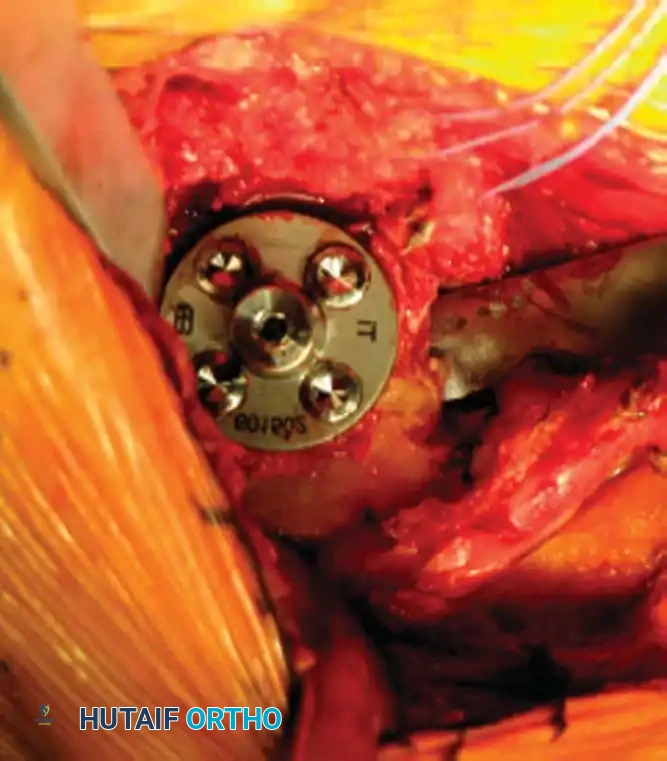

Reverse Total Shoulder Arthroplasty (rTSA)

The rTSA fundamentally alters shoulder biomechanics. By medializing and distalizing the center of rotation, it increases the deltoid moment arm and recruits more anterior and posterior deltoid fibers for elevation, bypassing the need for a functional rotator cuff.

Surgical Nuances for rTSA:

* Glenoid Baseplate: Must be positioned inferiorly on the glenoid to avoid scapular notching. A slight inferior tilt (10 degrees) is often utilized.

* Glenosphere: Typically 36 mm or 42 mm. Larger spheres increase stability and range of motion but may increase the risk of notching.

* Humeral Stem: Often placed in 0 to 20 degrees of retroversion.

Clinical Pearl: Tensioning is the most critical step in rTSA. The joint should be stable in all planes. If the joint dislocates easily, a thicker polyethylene insert or a larger glenosphere is required. However, over-tensioning can lead to acromial stress fractures or brachial plexopathy.

- Scapular Notching (rTSA): Mechanical impingement of the humeral component against the inferior scapular neck during adduction. Minimized by inferior placement and tilt of the glenosphere.